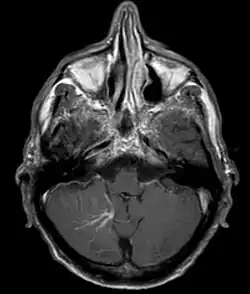

| Developmental venous anomaly in the cerebellum seen on axial contrast-enhanced T1 weighted MRI | |

A developmental venous anomaly (DVA, formerly known as venous angioma) is a congenital variant of the cerebral venous drainage. On imaging it is seen as a number of small deep parenchymal veins converging toward a larger collecting vein.

DVA can be characterized by the caput medusae sign of veins, which drains into a larger vein. The drains will either drain into a dural venous sinus or into a deep ependymal vein. It appears to look like a palm tree.[1]